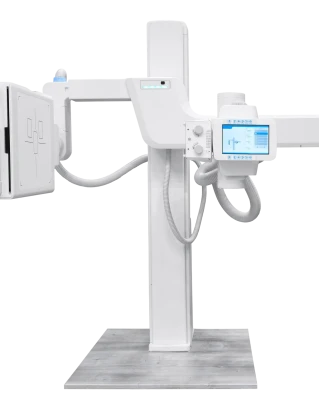

Badanie jest bezpieczne, dostępne i trwa zaledwie kilka minut. W CHH w Krakowie RTG kręgosłupa wykonywane jest na nowoczesnym cyfrowym sprzęcie z minimalną dawką promieniowania — wyniki dostępne są od razu po badaniu.

Terminowe wykonanie RTG odcinka kręgosłupa pozwala wykryć nawet minimalne odchylenia i zapobiec powikłaniom. W klinice CHH w Krakowie diagnostyka odbywa się na nowoczesnym cyfrowym sprzęcie — badanie trwa kilka minut, a wyniki dostępne są natychmiast po jego wykonaniu.